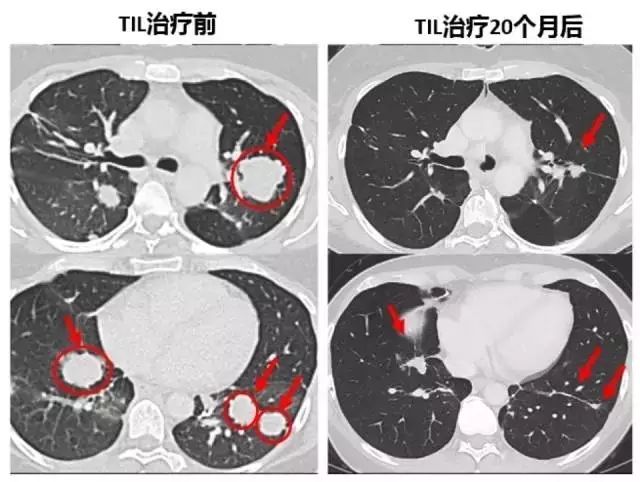

2018年6月,Barker接受治疗后获得了完全缓解,如今她已经买入了五年临床治愈的大门,处于无癌状态也超过了4年,她又带着潜水装备回到热爱的水中了。

Creelan博士激动的说,当我们启动这项研究时,我们从未期望看到完全缓解。这在肺癌中非常罕见。但是,有两名患者确实通过个性化TIL治疗获得了完全缓解,这意味着他们的扫描结果已经完全没有肿瘤。,一名是幸运的巴克大婶,另外一名幸运儿Pummill我们也在此前的文章中报道过,详情点击:两名患者完全缓解!新型免疫疗法给晚期肺癌患者带来新希望。

莫菲特癌症研究中心(H. Lee Moffitt )这项振奋人心的Ⅰ期临床试验结果,也在2020年的AACR大会上正式公布:在12名可评估的非小细胞肺癌患者中,TIL疗法可达到25%的总缓解率,其中2名患者达到持久的完全缓解。